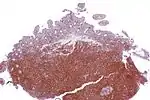

MCL is a subtype of B-cell lymphoma, due to CD5 positive antigen-naive pregerminal center B-cell within the mantle zone that surrounds normal germinal center follicles. MCL cells generally over-express cyclin D1 due to the t(11:14) translocation,[6] a chromosomal translocation in the DNA.

The most common B-cell type seen in MCL is a pre-germinal center cell (that has not yet undergone the germinal center reaction), that is CD5, CD20, CD19 positive with expression of IgM and IgD with monoclonal kappa and gamma light chains.[18] CD23 and CD200 are usually negative and cyclin-D1 (a cell cycle regulatory protein controlling transition from the G1 phase to the S phase in the cell cycle) is classically overexpressed in MCL.[18] SOX11 (a transcription factor controlling genes involved in cell survival) is characteristically over-expressed in MCL as well.[18] Ki-67, a marker of cell proliferation, if elevated (greater than 30% expression) is associated with an aggressive course of MCL.[18]